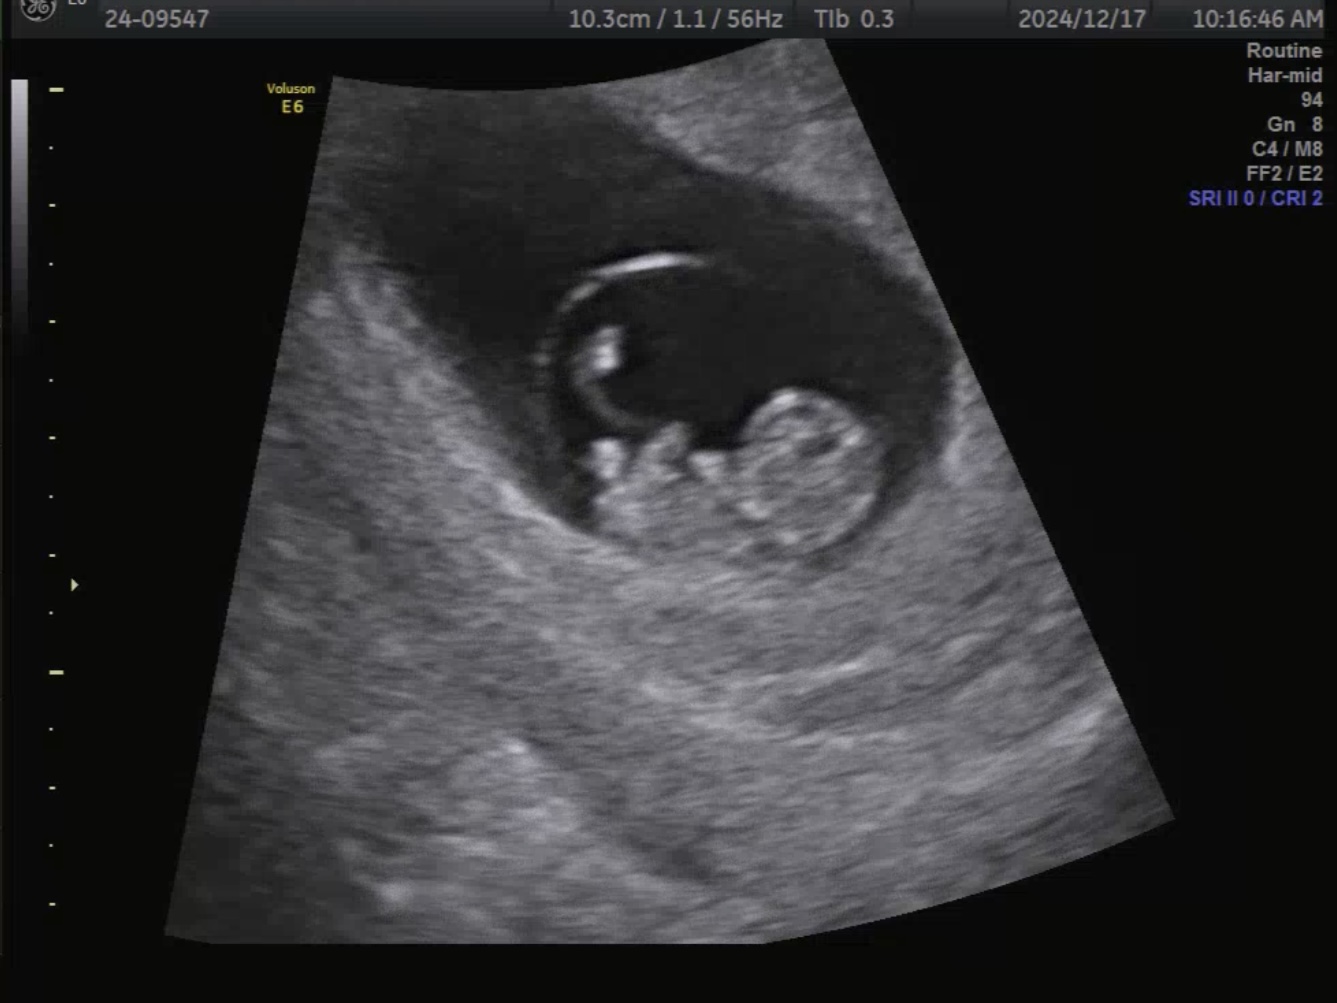

산부인과 정기진료 초음파

9주 2일차,

초음파 상 태아의 심장 박동수는

173bpm으로 규칙적으로 뛰고 있었고,

현재까지 별다른 이상 소견은 없었다.

태아는 하리보처럼 팔다리의 형태가

눈에 보이기 시작했다.